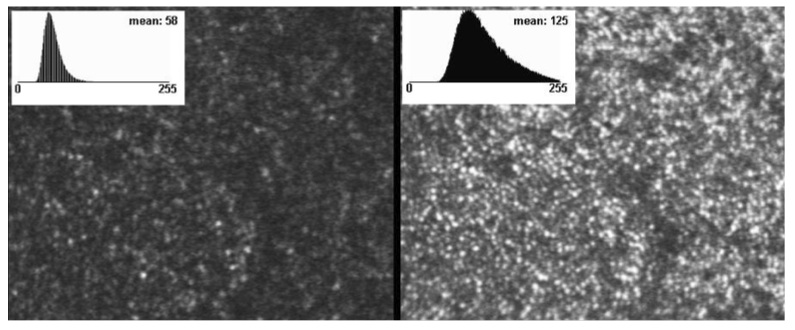

Adaptive optical correction allows one to obtain high-resolution images of the retina. The result is illustrated on Fig. 1: on the left panel, without AO correction, individual cells of the retina are unresolved. On the right panel, after AO correction the individual cones of the retina are distinguishable. These high-resolution images have allowed an improved understanding of the eye’s properties, notably of the photoreceptor distribution. One might have expected that the development of AO systems for the retina would lead to a wealth of publications on early-stage diagnoses of retinal diseases. This is however not the case, and we believe that a main reason is the small field size of AO corrected images.